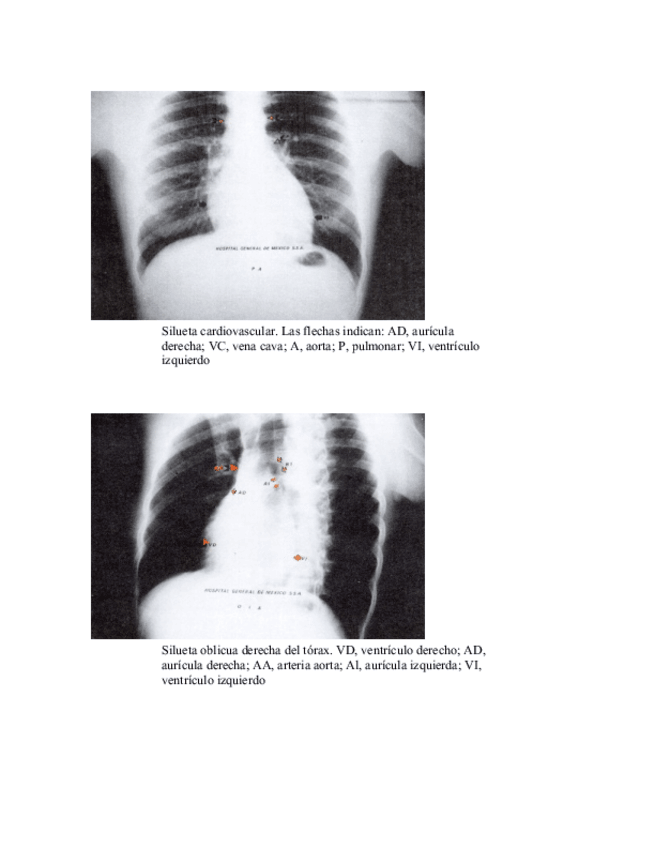

He publicado nuevos apuntes de 3º Prevenció i Tractament de Fisioteràpia en Processos Vasculars. Prevenció i Tractament del Linfedema: SILUETA-CARDIOVASCULAR.pdf